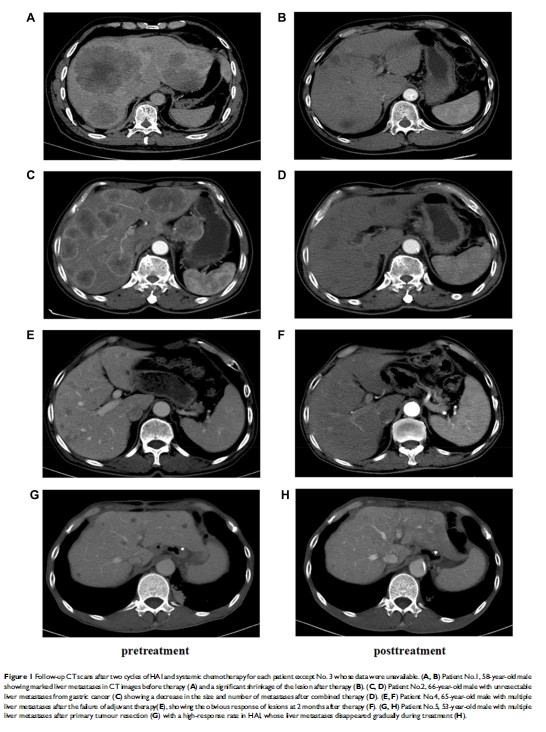

肝动脉输注奥沙利铂结合口服化疗药物 S-1 治疗无法切除的肝转移胃癌:病例报告和文献回顾